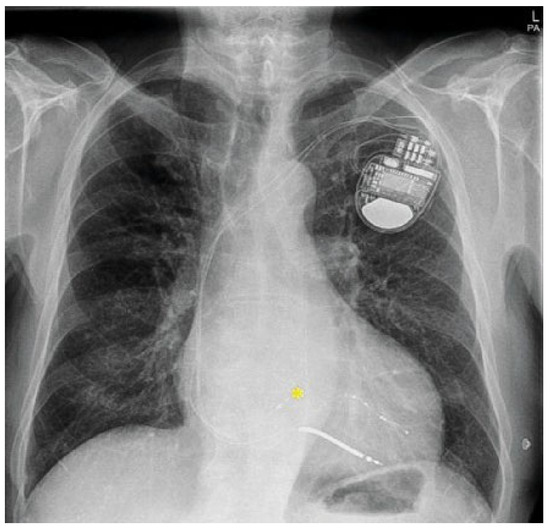

Permanent HIS bundle pacing—A valid alternative to biventricular cardiac resynchronization therapy?

by Gabriela Hilfiker, Kris Gillis, Louisa O’Neill, Jean-Yves Wielandts, Mattias Duytschaever, René Tavernier, Sébastien Knecht and Jean-Benoit Le Polain de Waroux

Cardiovasc. Med. 2022, 25(2), 53; https://doi.org/10.4414/cvm.2022.02188 - 1 Mar 2022

Cardiac resynchronisation therapy (CRT) using biventricular pacing has become standard of care for patients with symptomatic heart failure, wide QRS and left ventricular ejection fraction (LVEF) <35% refractory to optimal medical treatment. Convincing data have demonstrated improvement in quality of life as well as mortality rates in CRT responders. However, individual long-term response is difficult to predict as demonstrated by the usual 25–30% rate of non-response. Permanent His bundle pacing has emerged as an alternative to biventricular pacing to deliver physiological pacing as well as cardiac resynchronisation. We are presenting the case of a 78-year-old patient in whom resynchronisation using His bundle pacing translated into a clearly superior acute electrical result compared with biventricular pacing. Full article

Figure 1